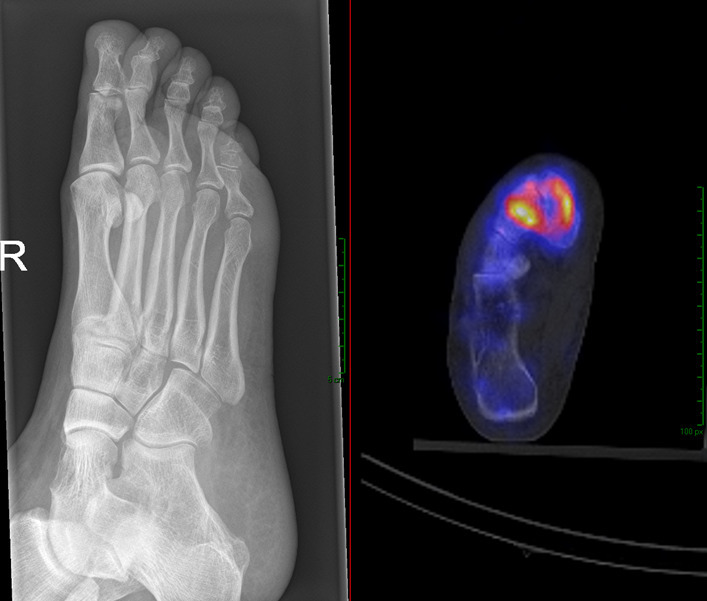

Abstract Image